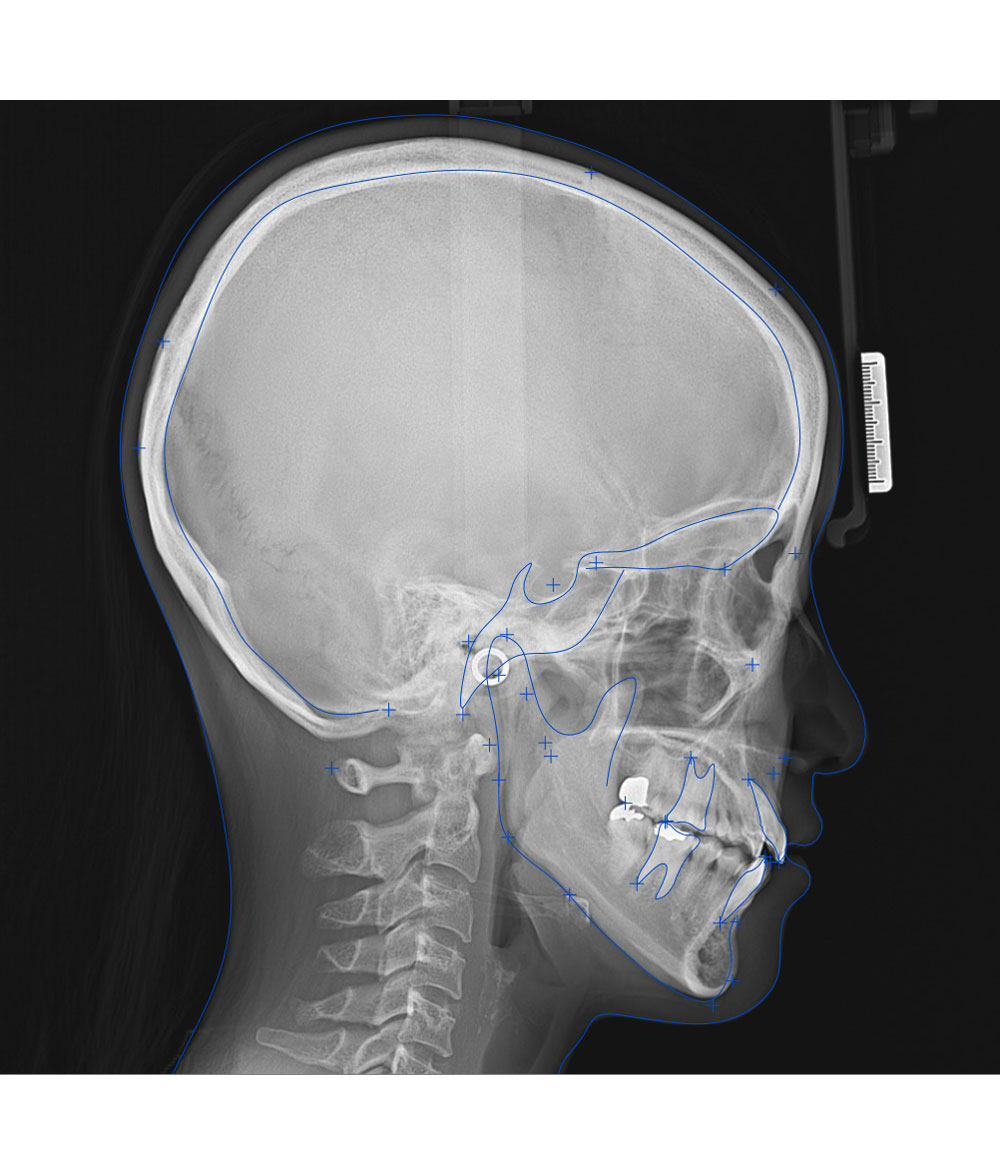

もう一つのレントゲンは、横顔を撮影する機械です。

頭を軽く固定した後、

こちらの機械も動くので真っ直ぐ正面を見てお待ちください。

このような横顔が撮れます。

次は、初診相談時に集めた情報を元にした

Dr.の診断結果をお伝えします。

前回の検査結果を分析し、最適な治療計画や治療費をお伝えします。